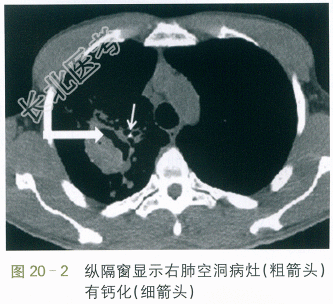

/L,N85.33%,Hb93.0g/L,CRP53.0mg/L,ESR45.0mm/h,肝肾功能电解质正常。HIV抗体、抗核抗体、癌胚抗原阴性;尿常规正常。 CT检查:右上肺见空洞,空洞内壁无液平,外周见斑片状影,纵隔窗显示空洞病灶有局限性钙化,左肺舌叶见小斑片状影伴支气管气象,右肺中叶也见少许渗出影伴小叶中心结节有树芽征。考虑两肺炎症,结核不能除外。如图20-1、图20-2、图20-3所示。